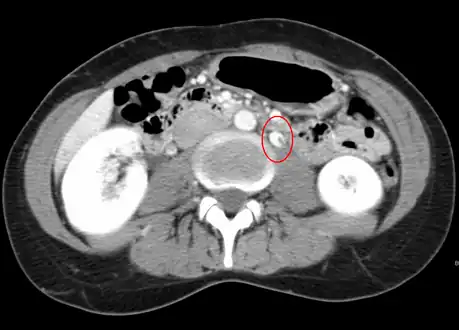

The nutcracker syndrome results from compression of the left renal vein between the aorta and the superior mesenteric artery.

Compression most commonly occurs between the abdominal aorta (AA) and superior mesenteric artery (SMA), though compression may also occur between the aorta and spine.[3][1] Risk factors include retroperitoneal cancers, abdominal aortic aneurysm, low body mass index, lordosis, and enlarged lymph nodes around the aorta.[1] Diagnostic may be suspected based on symptoms and confirmed by medical imaging after ruling out other possible causes.[1] Superior mesenteric artery syndrome is a different condition in which the duodenum is compressed between the the SMA and AA.[4]

Nutcracker syndrome is diagnosed through imaging such as doppler ultrasound (DUS), computed tomography (CT), magnetic resonance imaging (MRI), and venography.[15] The selection of the imaging modality is a step-wise process. DUS is the initial choice after clinical suspicion based on symptoms. CT and MRI are used to follow up afterwards, and if further conrfirmation is necessary, venography is used to confirm.[15]

CT and MRI

CT and MRI can be used afterward to confirm compression by the AA and SMA with comprehensive measurements of the abdominal vasculature. A "beak sign" can often be seen in CT scans due to the LRV compression. However, CT and MRI cannot demonstrate the flow within the compressed vein. These two modalities can be used to confirm other evidence for NCS such as back-up of blood flow into the ovarian veins.[14][9]